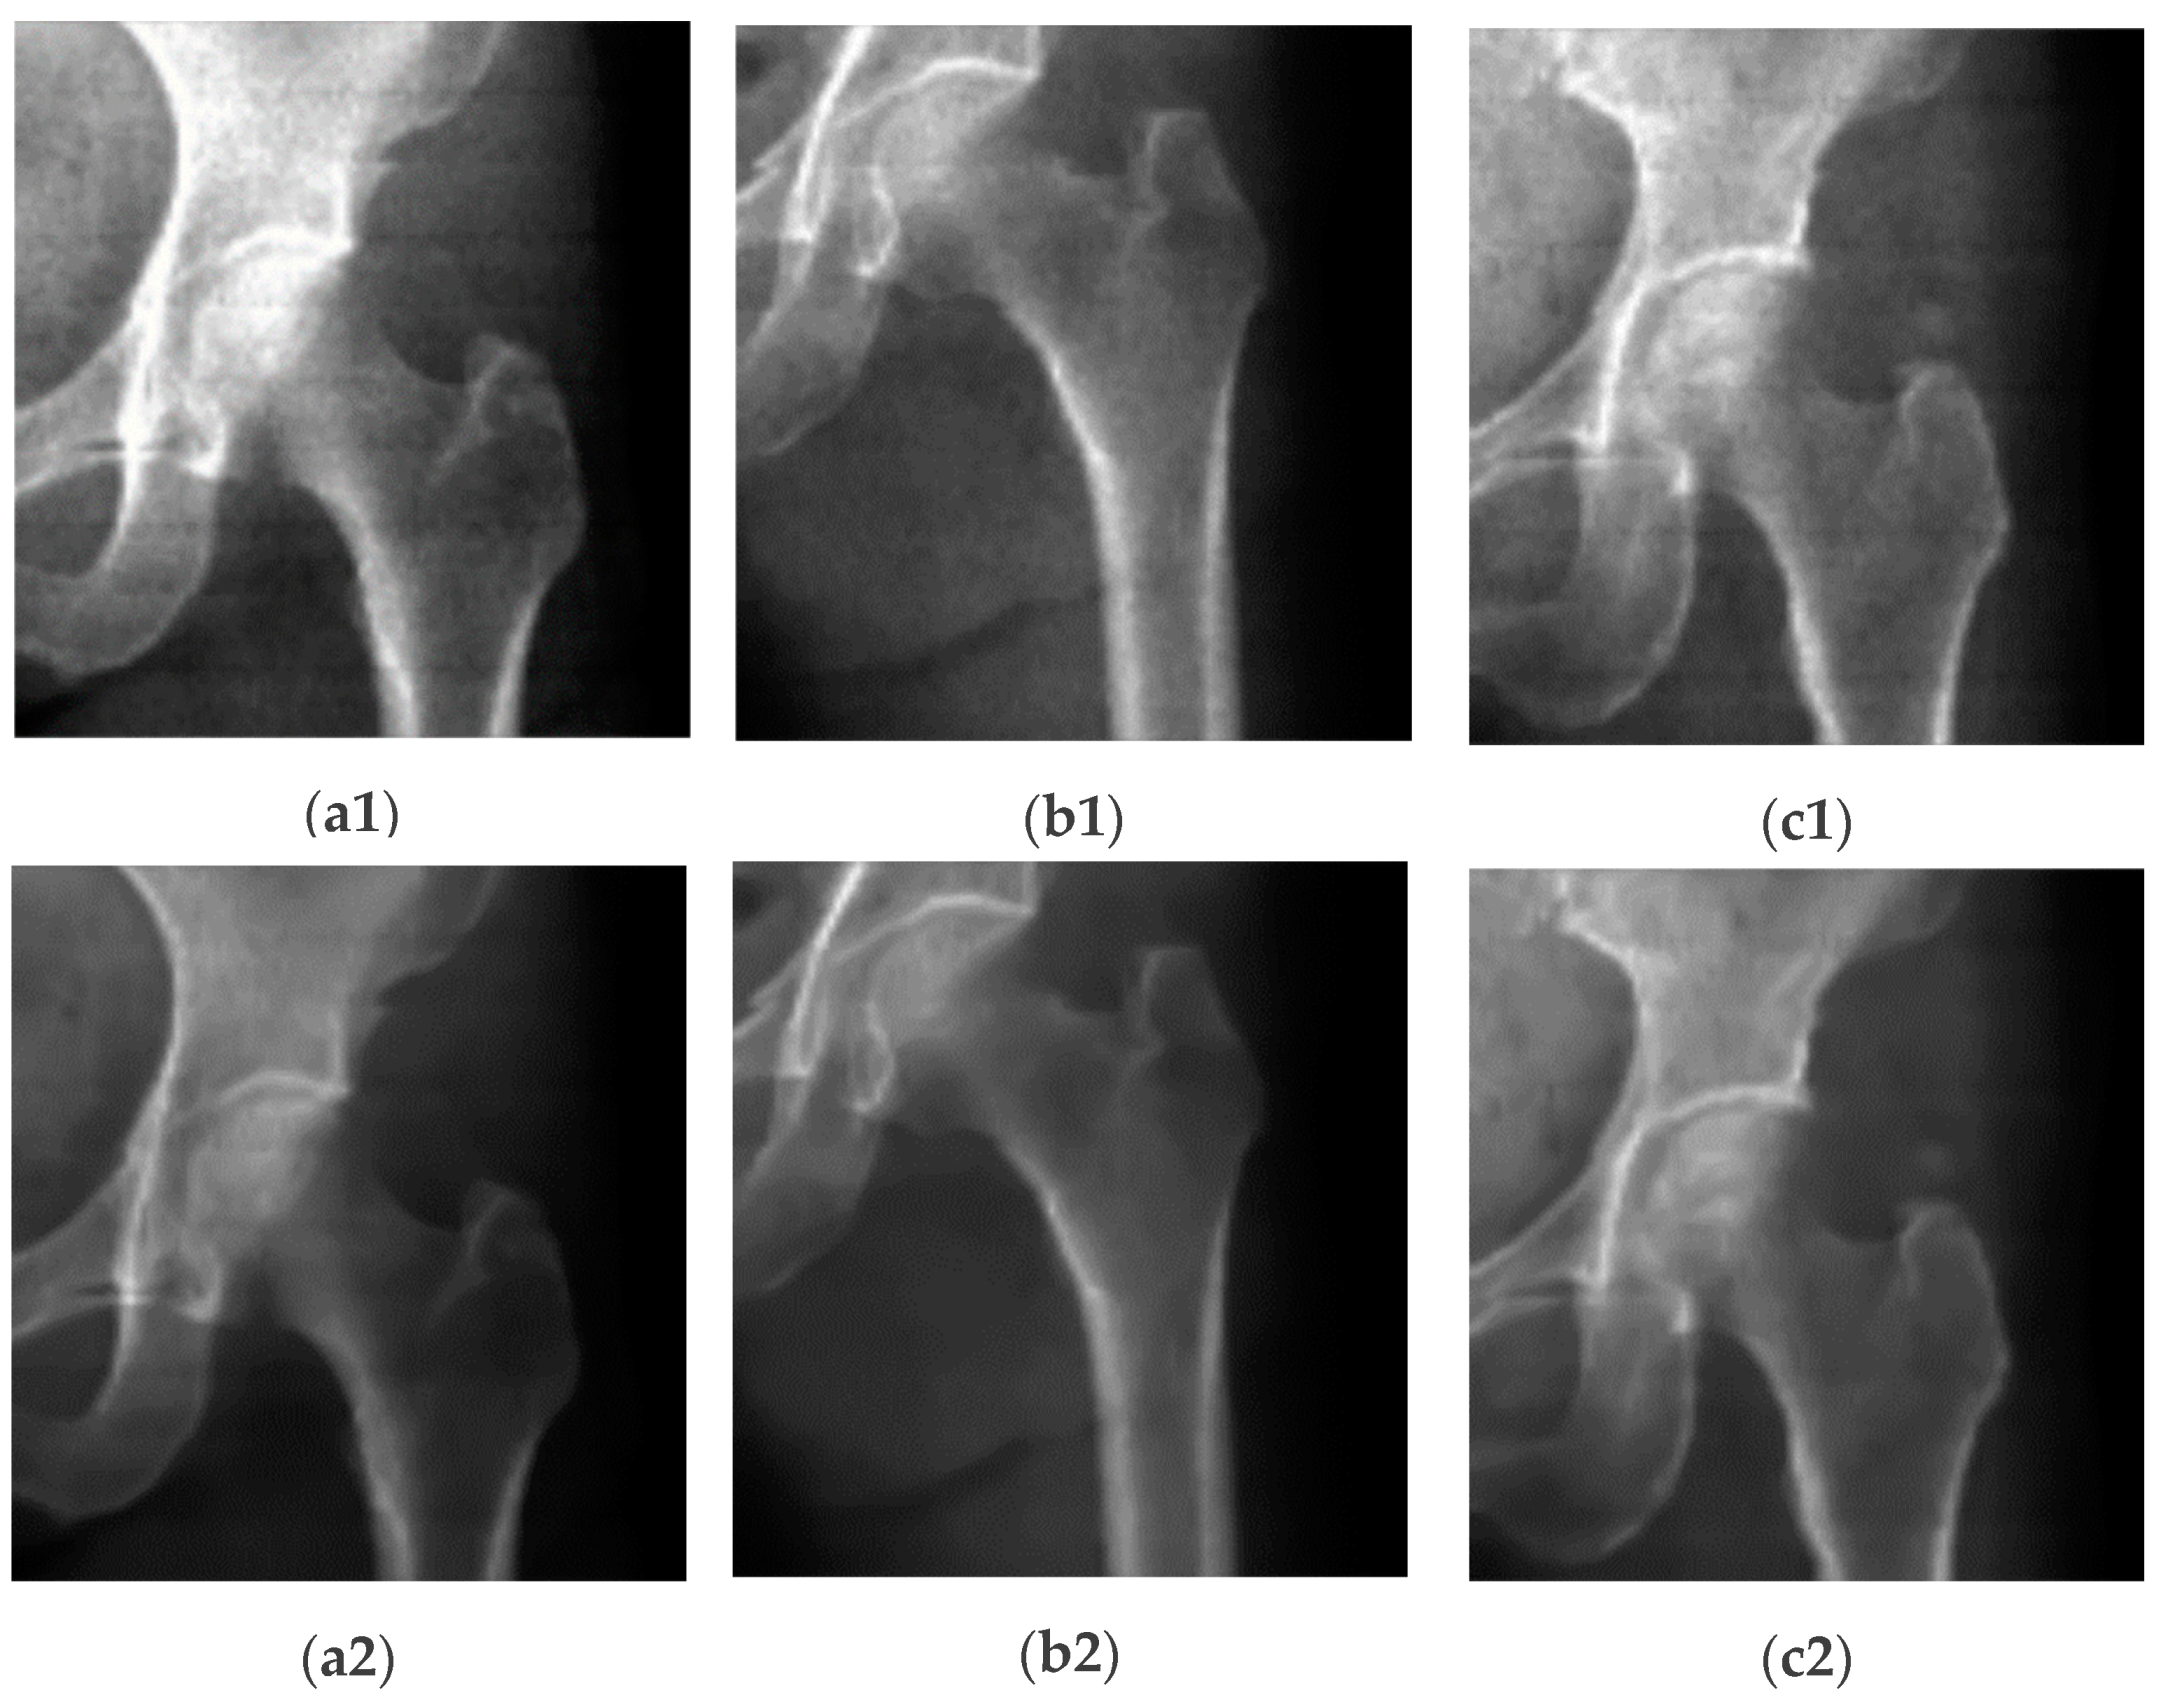

where ‘ δ ’ is the standard deviation (STD) of the log (LE/HE) ratio and ‘ μ ’ is the mean of the log (LE/HE). The values of B and C represent image brightness and contrast values to be obtained from experiments. From Equation (4), we get a very high-contrast image with clear boundaries between different regions (i.e., bone, soft tissues, and air) compared to IBD and ILR. As we see from Figure 2, some information (most probably an artifact), indicated by red arrows in Figure 2(a2,a3), is hidden which appears in the CI and IBD images, as indicated by red arrows in Figure 2(c1,c3). So, CI gives a very high-contrast image with detailed DXA scan information. One drawback of the ILR image is that when an image contains an artifact, the image appears very black, as shown in Figure 2(c2). This problem does not affect CI images, as we see in Figure 2(c3). We normalize the intensities of the image from 0 to 255, and the final image is saved in ‘.png’ format to be used in the DL model.

Figure 2. Generated high-contrast images from DXA scan. In this figure (a1,b1,c1) are IBD images, (a2,b2,c2) represent ILR images, and (a3,b3,c3) represent high contrast CI images. As indicated by the arrows, some information is hidden at the arrow positions in the ILR images, while this information is revealed in the CI images. We primarily use CI for the final segmentation of DXA images. These collage images are created by combining high-energy (HE) and low-energy (LE) images, enhancing the contrast and improving segmentation performance. Bone mineral density is calculated from the HE and LE images using different algorithms as in Equations (1) and (2).